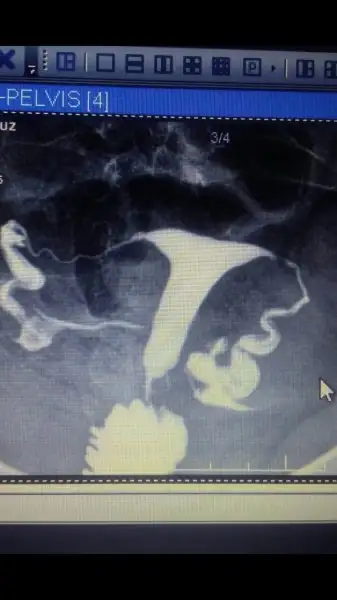

Arkadaslar geçen hafta hsg çektirdi 3/4 Ayrı doktora filmi mi gösterdim her doktor farklı şey söylüyor biri hersey normal diğeri rahmin t seklinde histeroskopi olmasi lazim diyor başka bir doktor rahmin t değil sol tupte sivi birikmesi var laposokopi olmadı gerekir diyor hangi doktora inanacagimi şaşırdım bence gerckten bu rahim filmleri iice araştırılıp bir kaç doktora danisilmali rahim filmi mi gonderyrm benm filmim gibi olan varmı aranızda ??iice moralim bozuldu

Resmi şimdi yukleyebildim

Eklentiler

• IMG-20170528-WA0001.webp

IMG-20170528-WA0001.webp

10,7 KB · Görüntüleme: 132